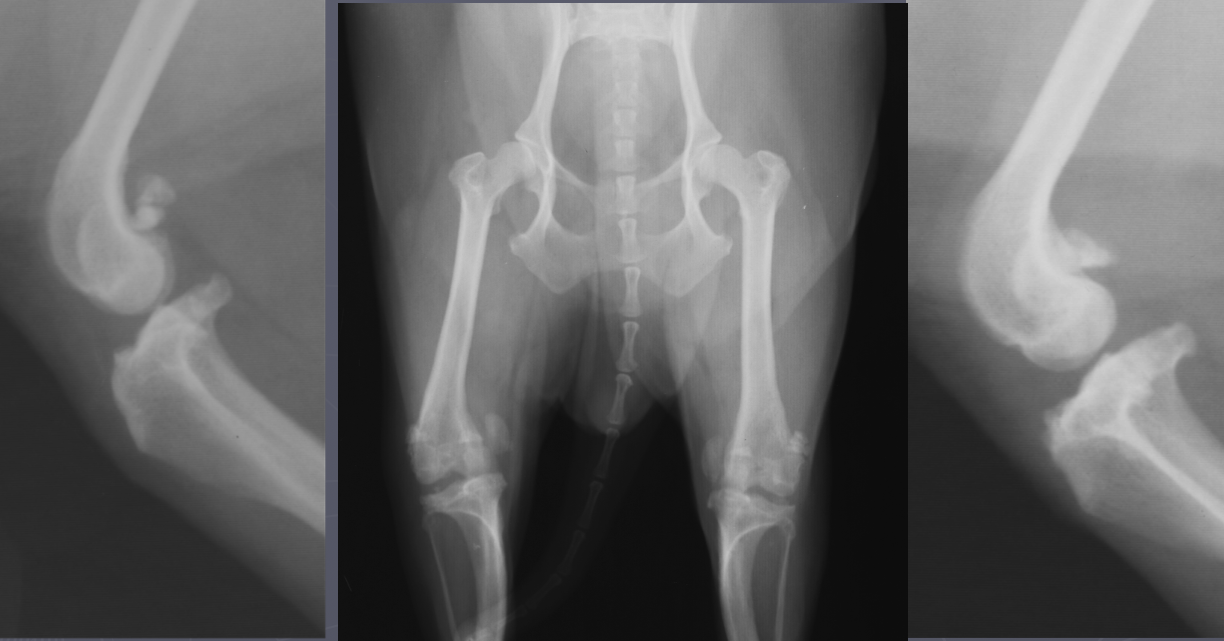

Metaphyseal osteopathy signalment

2-7 mo age

large giant breeds

systemically ill

bilateral/all 4 limbs

double physeal sign ± cuff

Metaphyseal osteopathy